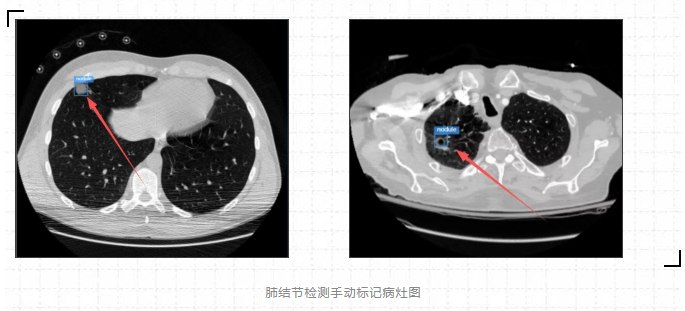

箭头指的地方可看见检测结果,可以说利用ModelArts平台训练出来的肺结节检测模型检测效果是很棒的。(直接看太小的话,可以点开图片放大看)

从最后实验的结果对比图来看,可以说利用ModelArts平台训练出来的肺结节检测模型检测效果是很棒的,虽然存在一定的肺结节病灶假阳性标记,但是这在小样本数据集的人工智能医疗检测中是会出现的情况。毕竟对于人工智能医疗检测模型来说,只用了300张标注图片就能达到这样的效果,真的让人感到惊喜。